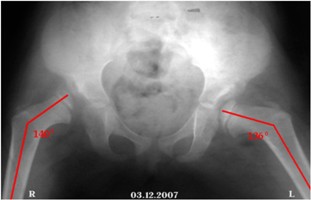

Клинический пример. Больная К., 4 года, поступила в отделение детской ортопедии и травма-тологии 03.12.2007. Поступила с жалобами на боли, хромату и ограничения движений. Лечения до поступления не получала. На момент поступления имелась следующая рентгенологическая картина (рис. 1а,б).

а б

Рис. 1а,б. Рентгенограмма таза. Врожденный вывих правого бедра, подвывих левого. Переднезадняя проекция

- а - нейтральная позиция. Красным указанны шеечно-диафизарные углы до операции (правый – 1600 и левый – 1410). Зеленым указаны ацетабулярные углы до операции (правый – 370 и левый – 430).

- б - Отведение и внутренняя ротация. Красным указанны шеечно- диафизарные углы до операции (правый – 1400 и левый – 1360). Угол патологической антиторсии справа–650, слева – 300.